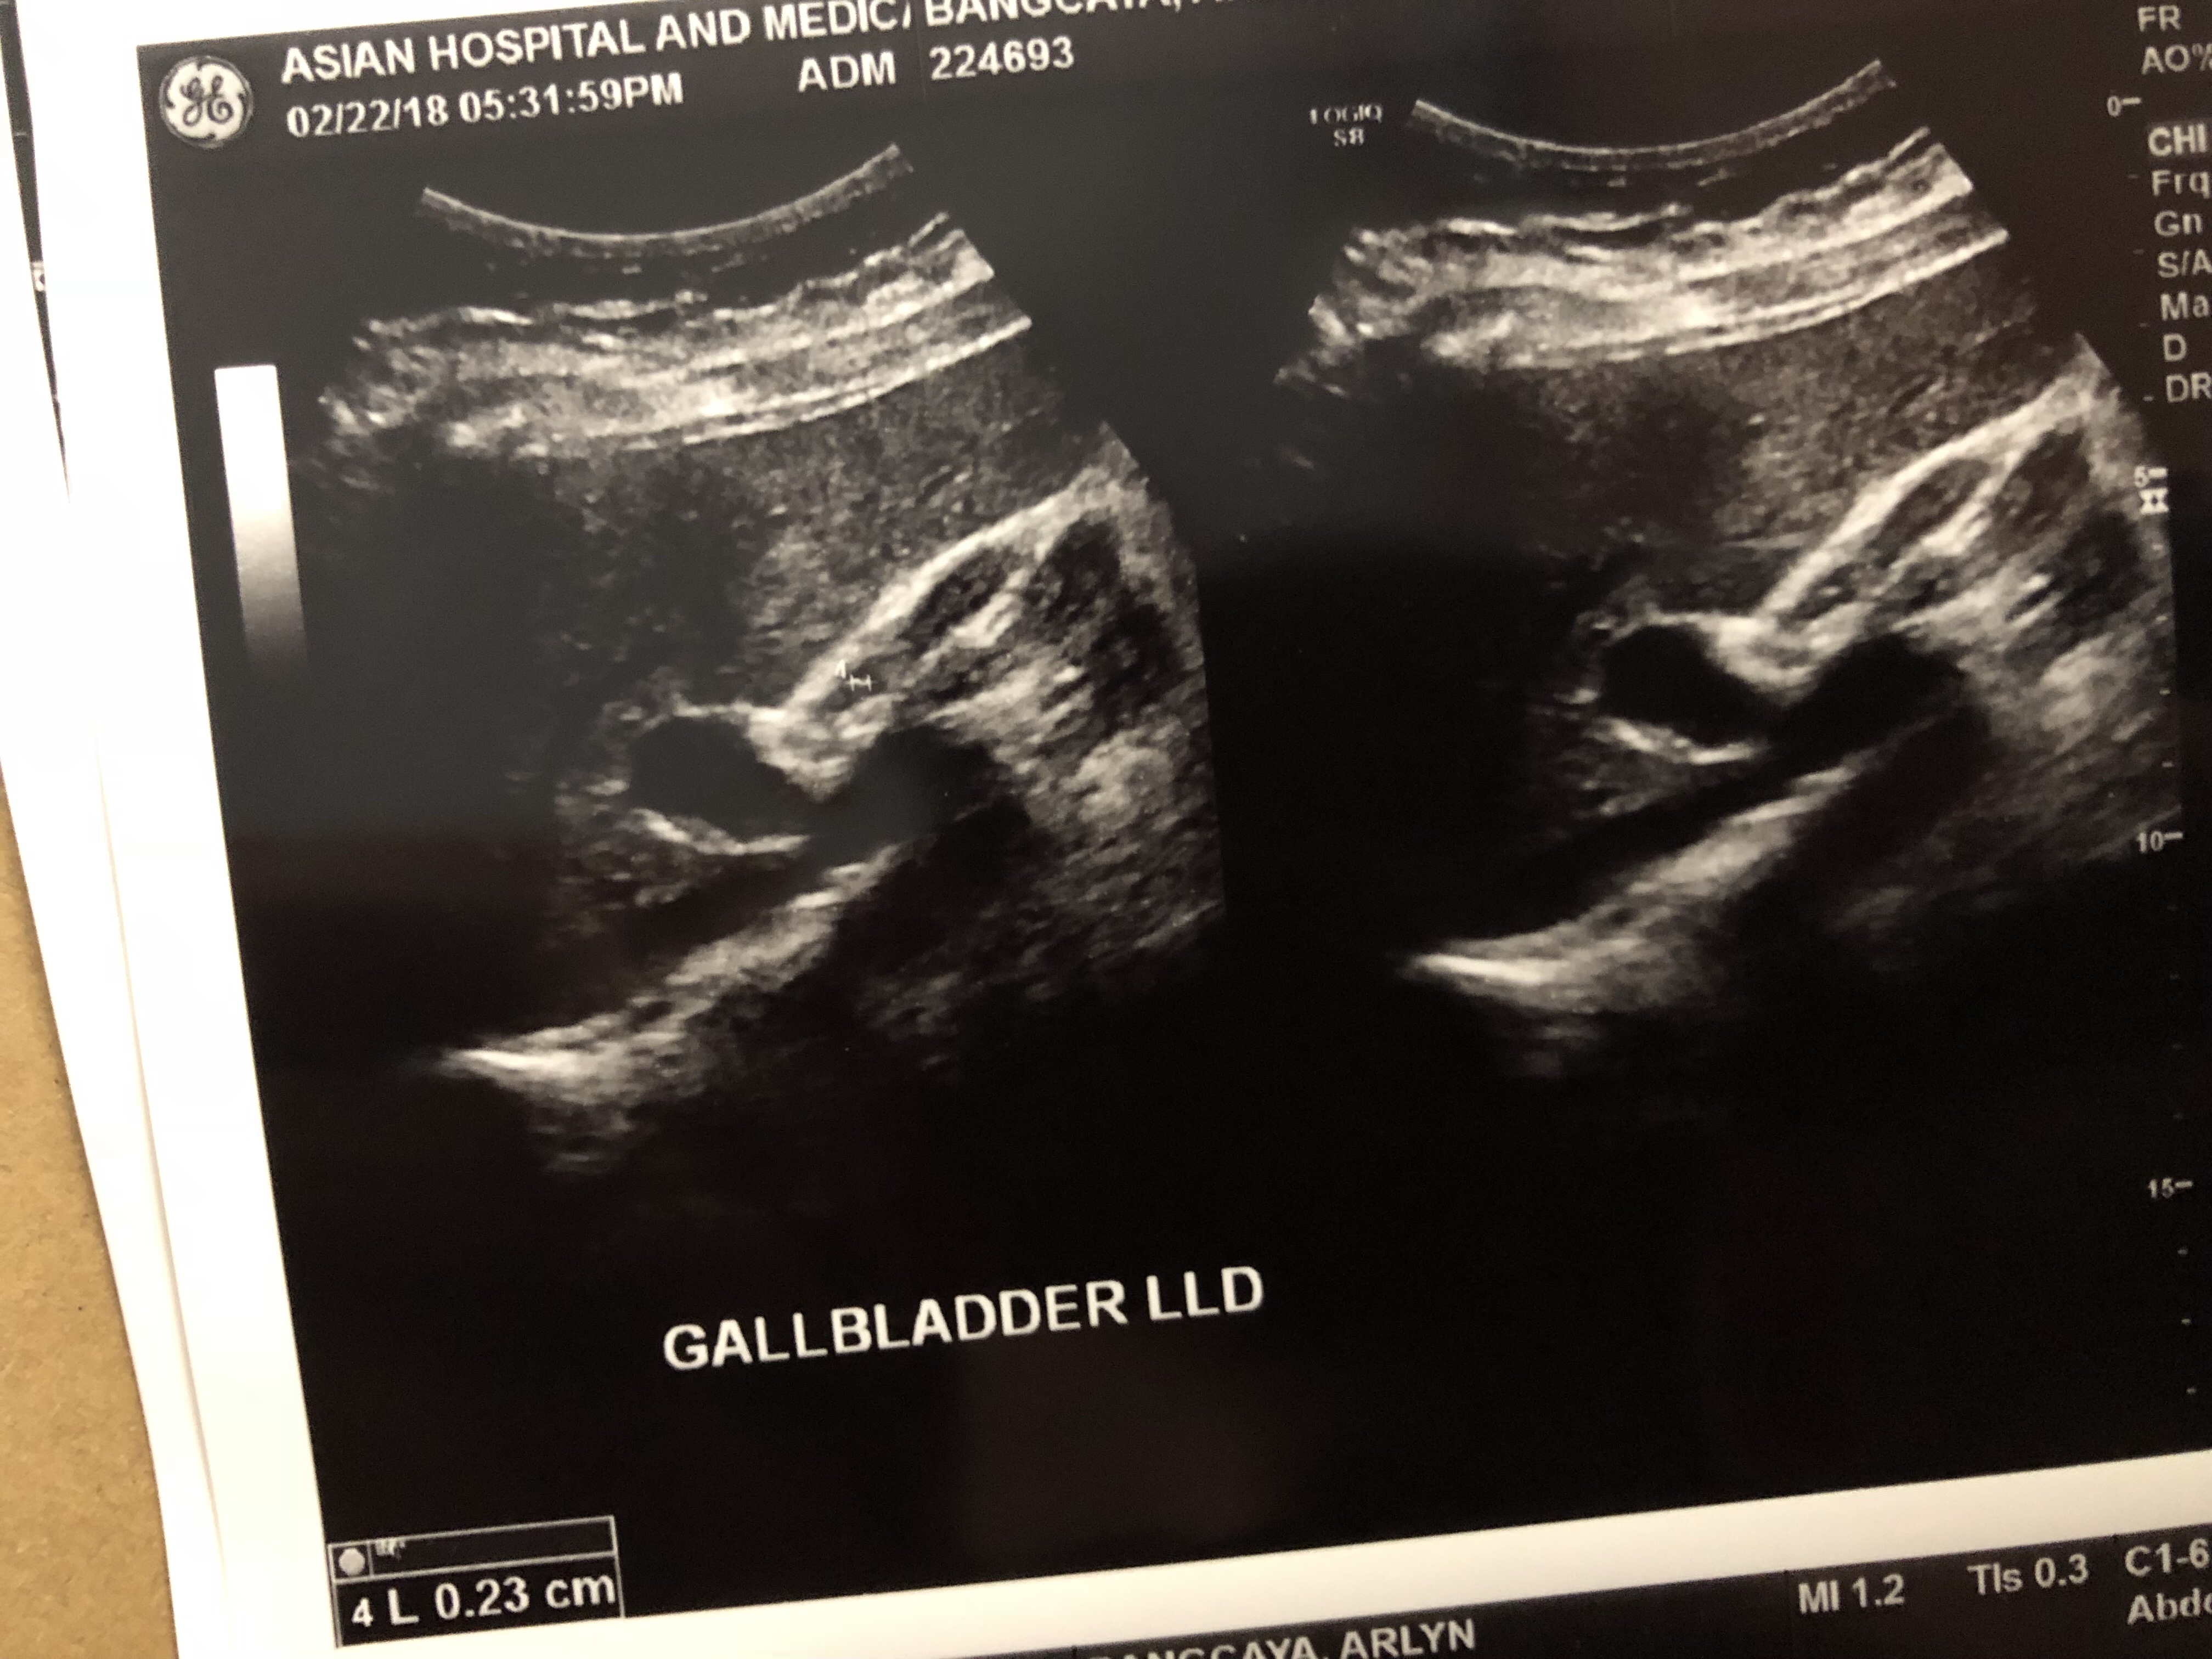

Lastly the Gall bladder, if you see that pear shape image that’s the it and it lies beneath the liver